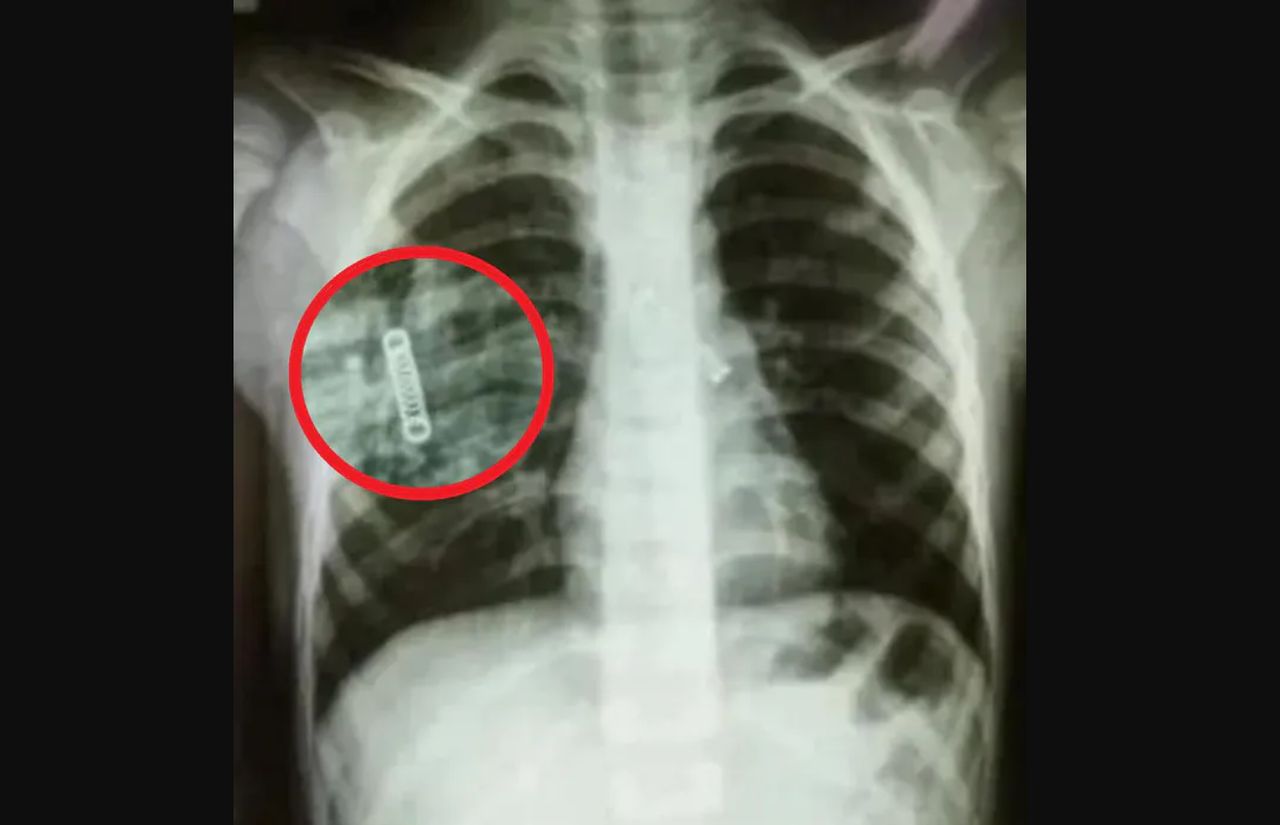

Każda forma antykoncepcji niesie ze sobą ryzyko wystąpienia skutków ubocznych bądź powikłań. 29-latka z Nottinghamshire w środkowej Anglii doświadczyła migracji implantu antykoncepcyjnego. Kiedy po trzech latach poszła go wyciągnąć, okazało się, że jest to niemożliwe. Implant przemieścił się i utknął... w płucu.

W lutym 2022 r. Rebecca poznała prawdę - implant dotarł do tętnicy płucnej. Od lekarzy usłyszała, że teoretycznie można go usunąć, ale taka procedura jest niebezpieczna i nie ma pewności, że się uda. Co więcej, próba usunięcia mogłaby rozerwać tętnicę, w której się znajduje. Z uwagi na to, że implant nie sprawiał żadnych problemów, kobieta zdecydowała się pozostawić go w organizmie. Bała się podejmować ryzyko, ponieważ jest już mamą dwójki dzieci: 7-letniego Dextera oraz 6-letniej Lexxie.

W dokumentach medycznych Rebecca przeczytała, że implant antykoncepcyjny "zatrzymał się w gałęzi tętnicy płucnej lewego płuca". Najprawdopodobniej stało się to już w momencie wszczepienia lub niewiele później. To niezwykle rzadkie powikłanie, które (według brytyjskiej Agencji Regulacyjnej ds. Leków i Produktów Opieki Zdrowotnej) występuje u jednej na 1,3 miliona kobiet.